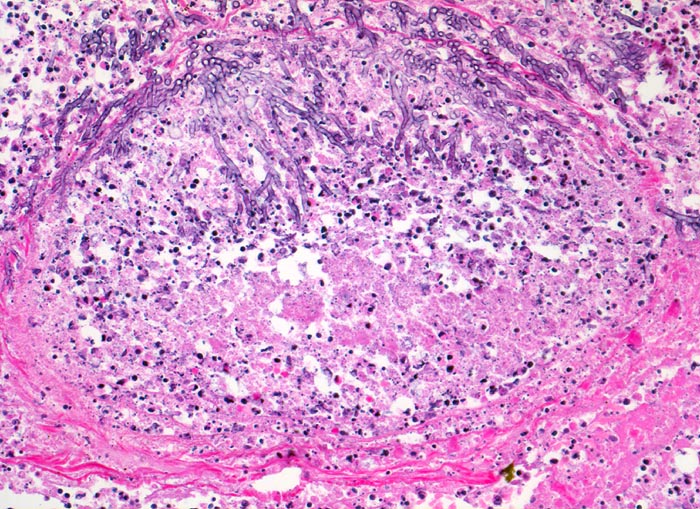

Aspergillus unterscheidet sich von anderen Pilzen (> 1462) (> 712) durch häufige Verzweigungen der Hyphen in einem Winkel von 45°, die radiär in grossen Kolonien liegen (> 547) (> 556). Besonders gut sind die Pilze in der PAS (> 717) und in der Grocott (> 189) Färbung nachweisbar. Die vier häufigsten durch Aspergillen hervorgerufenen Lungenerkrankungen sind die allergische bronchopulmonale Aspergillose, die chronische nekrotisierende Aspergilluspneumonie, das Aspergillom oder wie in diesem Fall die invasive Aspergillose. (Näheres zu den verschiedenen Krankheitsbildern im Literaturlink). Bei Immunsupprimierten invadieren die Pilze häufig die Gefässe. Dies führt zu Infarkten, Blutungen und Nekrosen der Lunge. Über die Invasion der Gefässe kommt es zur septischen Streuung (> 715) (> 49) im grossen Kreislauf.

Morphologische Merkmale:

• Multiple Herde mit zentraler Nekrose und hämorrhagischem Randsaum.

• Pilzmyzelien, zerfallende neutrophile Granulozyten und Erythrozyten im Zentrum der Herde.

• Kräftig gefärbte Pilzhyphen mit 45° Verzweigungen.

• Hämorrhagischer Randsaum um die Nekrose: Hyperämische Alveolarwandkapillaren. Alveolen angefüllt mit Blut, Fibrin und Alveolarmakrophagen.